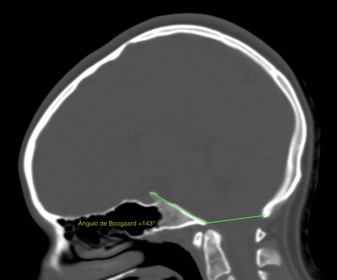

Elle est connue sous le nom de Platybasie (PTB) l’anomalie osseuse consistante dans l’aplatissement le la base du crâne, ce qui entraîne l’ouverture de l’angle basal de Boogard. La valeur normale de cet angle est comprise entre 115º et 140º. Il y a une platybasie lorsque l’angle dépasse les 140º. D’autres angles de référence peuvent également être pris en compte, par exemple celui de Bull (normale à 13º).

Pour le diagnostic et le contrôle de Platybasie, le crâne est visualisé avec une Tomodensimétrie crânial. Un diagnostic peut également être faite par imagerie par résonance magnétique – IRM encéphalique ou crânial, mais, une fois détectée, pour un contrôle optimal de la malformation, le TDM est indiqué.

Fig. 1 IImage Platybasie dans un TDM.